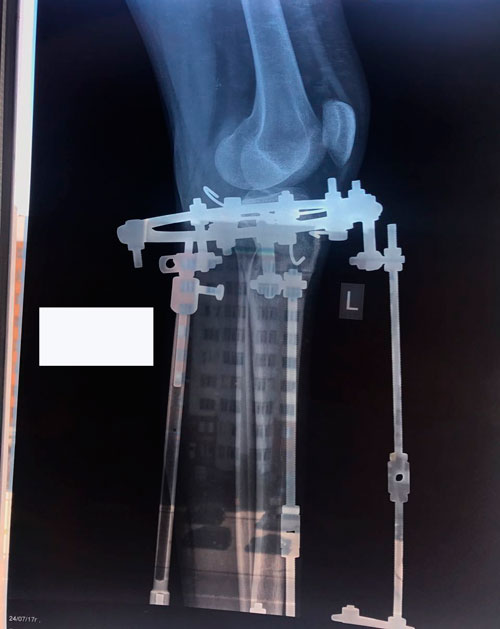

Исходник - 19 лет.

Дата операции 25.05.2017г.

В процессе круток

58 дней.

Через 2 недели можно на снятие аппаратов.

Срок лечения 75 дней.